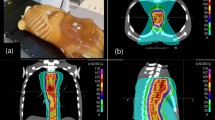

Variation of tumor volumes

The tumor volumes variation of the GTVmean, the IGTVMIP and the IGTV10 during radiotherapy are listed in Table 4. The tumor volume showed a trend of decline during the entire treatment, the change trend of GTVmean, IGTVMIP, and IGTV10 are completely consistent. At the tenth fraction, the volume of GTVmean, IGTVMIP, and IGTV10 decreased, but the variations are not significant compared to primary volumes for the upper, middle and distal tumor locations. For the GTVmean, volumes are increased 22.41% in 7 of 32 patients (range, 4.20%-39.42%), differences are statistically significant (P = 0.003). At the twentieth fraction, tumor volumes shrink further more, for all of the tumors, the volume of GTVmean, IGTVMIP, and IGTV10 decreased significantly relative to those of primary volumes (P = 0.000, P = 0.000 and P = 0.000, respectively). For the middle location, the GTVmean volume decreased 34.01% (range, 13.45%-63.28%, P = 0.009), IGTVMIP 33.09% (range, 6.00%-58.00%, P = 0.007), IGTV10 28.71% (range, 2.00%-54.00%, P = 0.012). For the distal esophageal cancer, GTVmean volume decreased 22.76% (range, 14.01%-50.64%, P = 0.047), IGTVMIP 25.27% (range, 9.00%-48.00%, P = 0.024), IGTV10 23.96% (range, 11.00%-51.00%, P = 0.029). But for the upper location, no significant reduction to the volume of GTVmean, IGTVMIP, and IGTV10 (P = 0.079, P = 0.082, and P = 0.164, respectively). Figure 1 showed the absolute volumetric changes of the GTVmean during 3DCRT/IMRT.